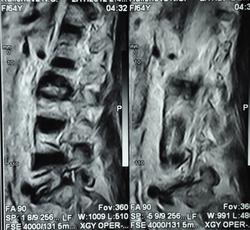

Можно гадать, но без клиники и анамнеща никак. Исходя из картинок больше на пиогенный вроде. Хотя, и тубер может выглядеть так же.

Наверное, правильнее это можно назвать спондилодисцитом ( не туберкулезной этиологии)

Мне видится здесь последствия зверского дисцита.  Предположу, ситуация не острая - данных за отек соответсвующих позвонков нет, хотя для убедительности нужен FatSat.  Из этого делаем вывод- на первое место исход воспаления, с формированием кистозных изменений, на второе - быть может нечто постравматическое с последующим, опять же, дисцитом.

При пункция патологического участка позвоночника - Лимфома позвоночника. Передан онкологам на лечение.

Уважаемый Николас, диагностировать лимфому по представленным сканам-высший пилотаж.Аксиалы, короналы напрочь отсутствуют-как можно обнаружить паравертебральный мягкотканный компонент ( если он имеет место быть, конечно)????.А вот явные признаки спондилодисцита имеются.

Уважаемые коллеги, по мне так МРТ-картина нетипична для лимфомы. Это не значит, что это не лимфома, но всё же не похоже, если проанализировать имеющиеся признаки.

По мне так спондилодисцит. Характерный жидкостной сигнал в диске, деструкция смежных позвонков. А уж какой этиологии, это пусть клиницисты решают.